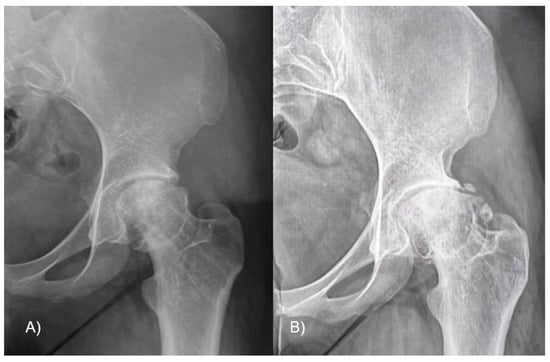

To evaluate the hip function, we used the Harris Hip Score (HHS) and hip joint articulation in the pre-operative period and at 3 and 6 months and 1 and 8 years follow-up. Anteroposterior and frog-leg lateral X-ray views were taken preoperatively and then at 4 weeks, 6 months, and yearly after. The level of slippage [] was recorded in the pre-operative period and at last follow-up (Figure 3). The lateral α angle [] and the epiphyseal–metaphyseal offset [] were also evaluated preoperatively and at the latest follow-up.

Figure 3.

A 12-year-old male patient affected by SCFE, with great deformity of the proximal femur, with a varus (A) and retroverted (B) neck. The femur after the surgery, with the correction in the coronal (C) and sagittal planes (D); the screws in both views are in the bone and not protrude into the joint. The final X-ray follow-up at 8 years shows the outcome of removing screws and the radiological good hip joint status (E).